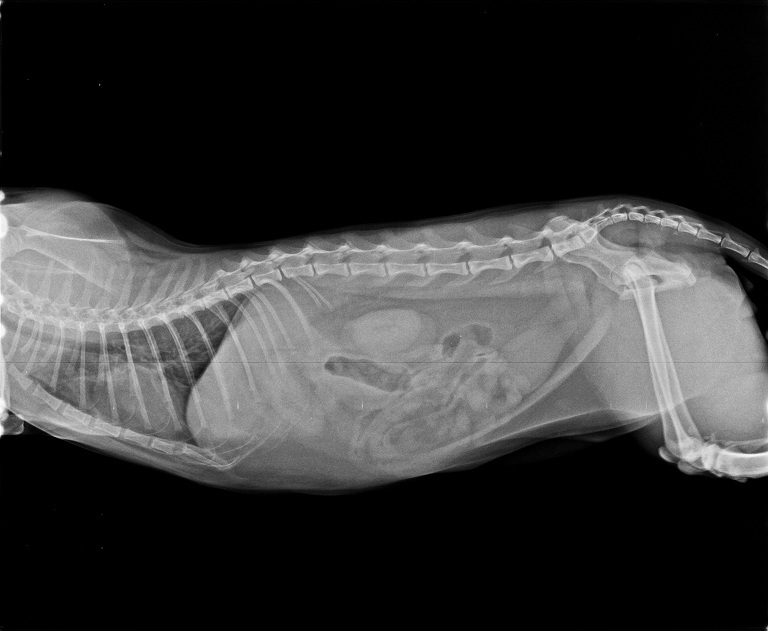

小樹在住院期間做了非常詳盡的各項檢查,

包括全套血檢、心絲蟲檢測,

並且做了先前沒做過的愛滋白血快篩,

也拍了X光照片確認小樹是否有吞下不尋常的異物。